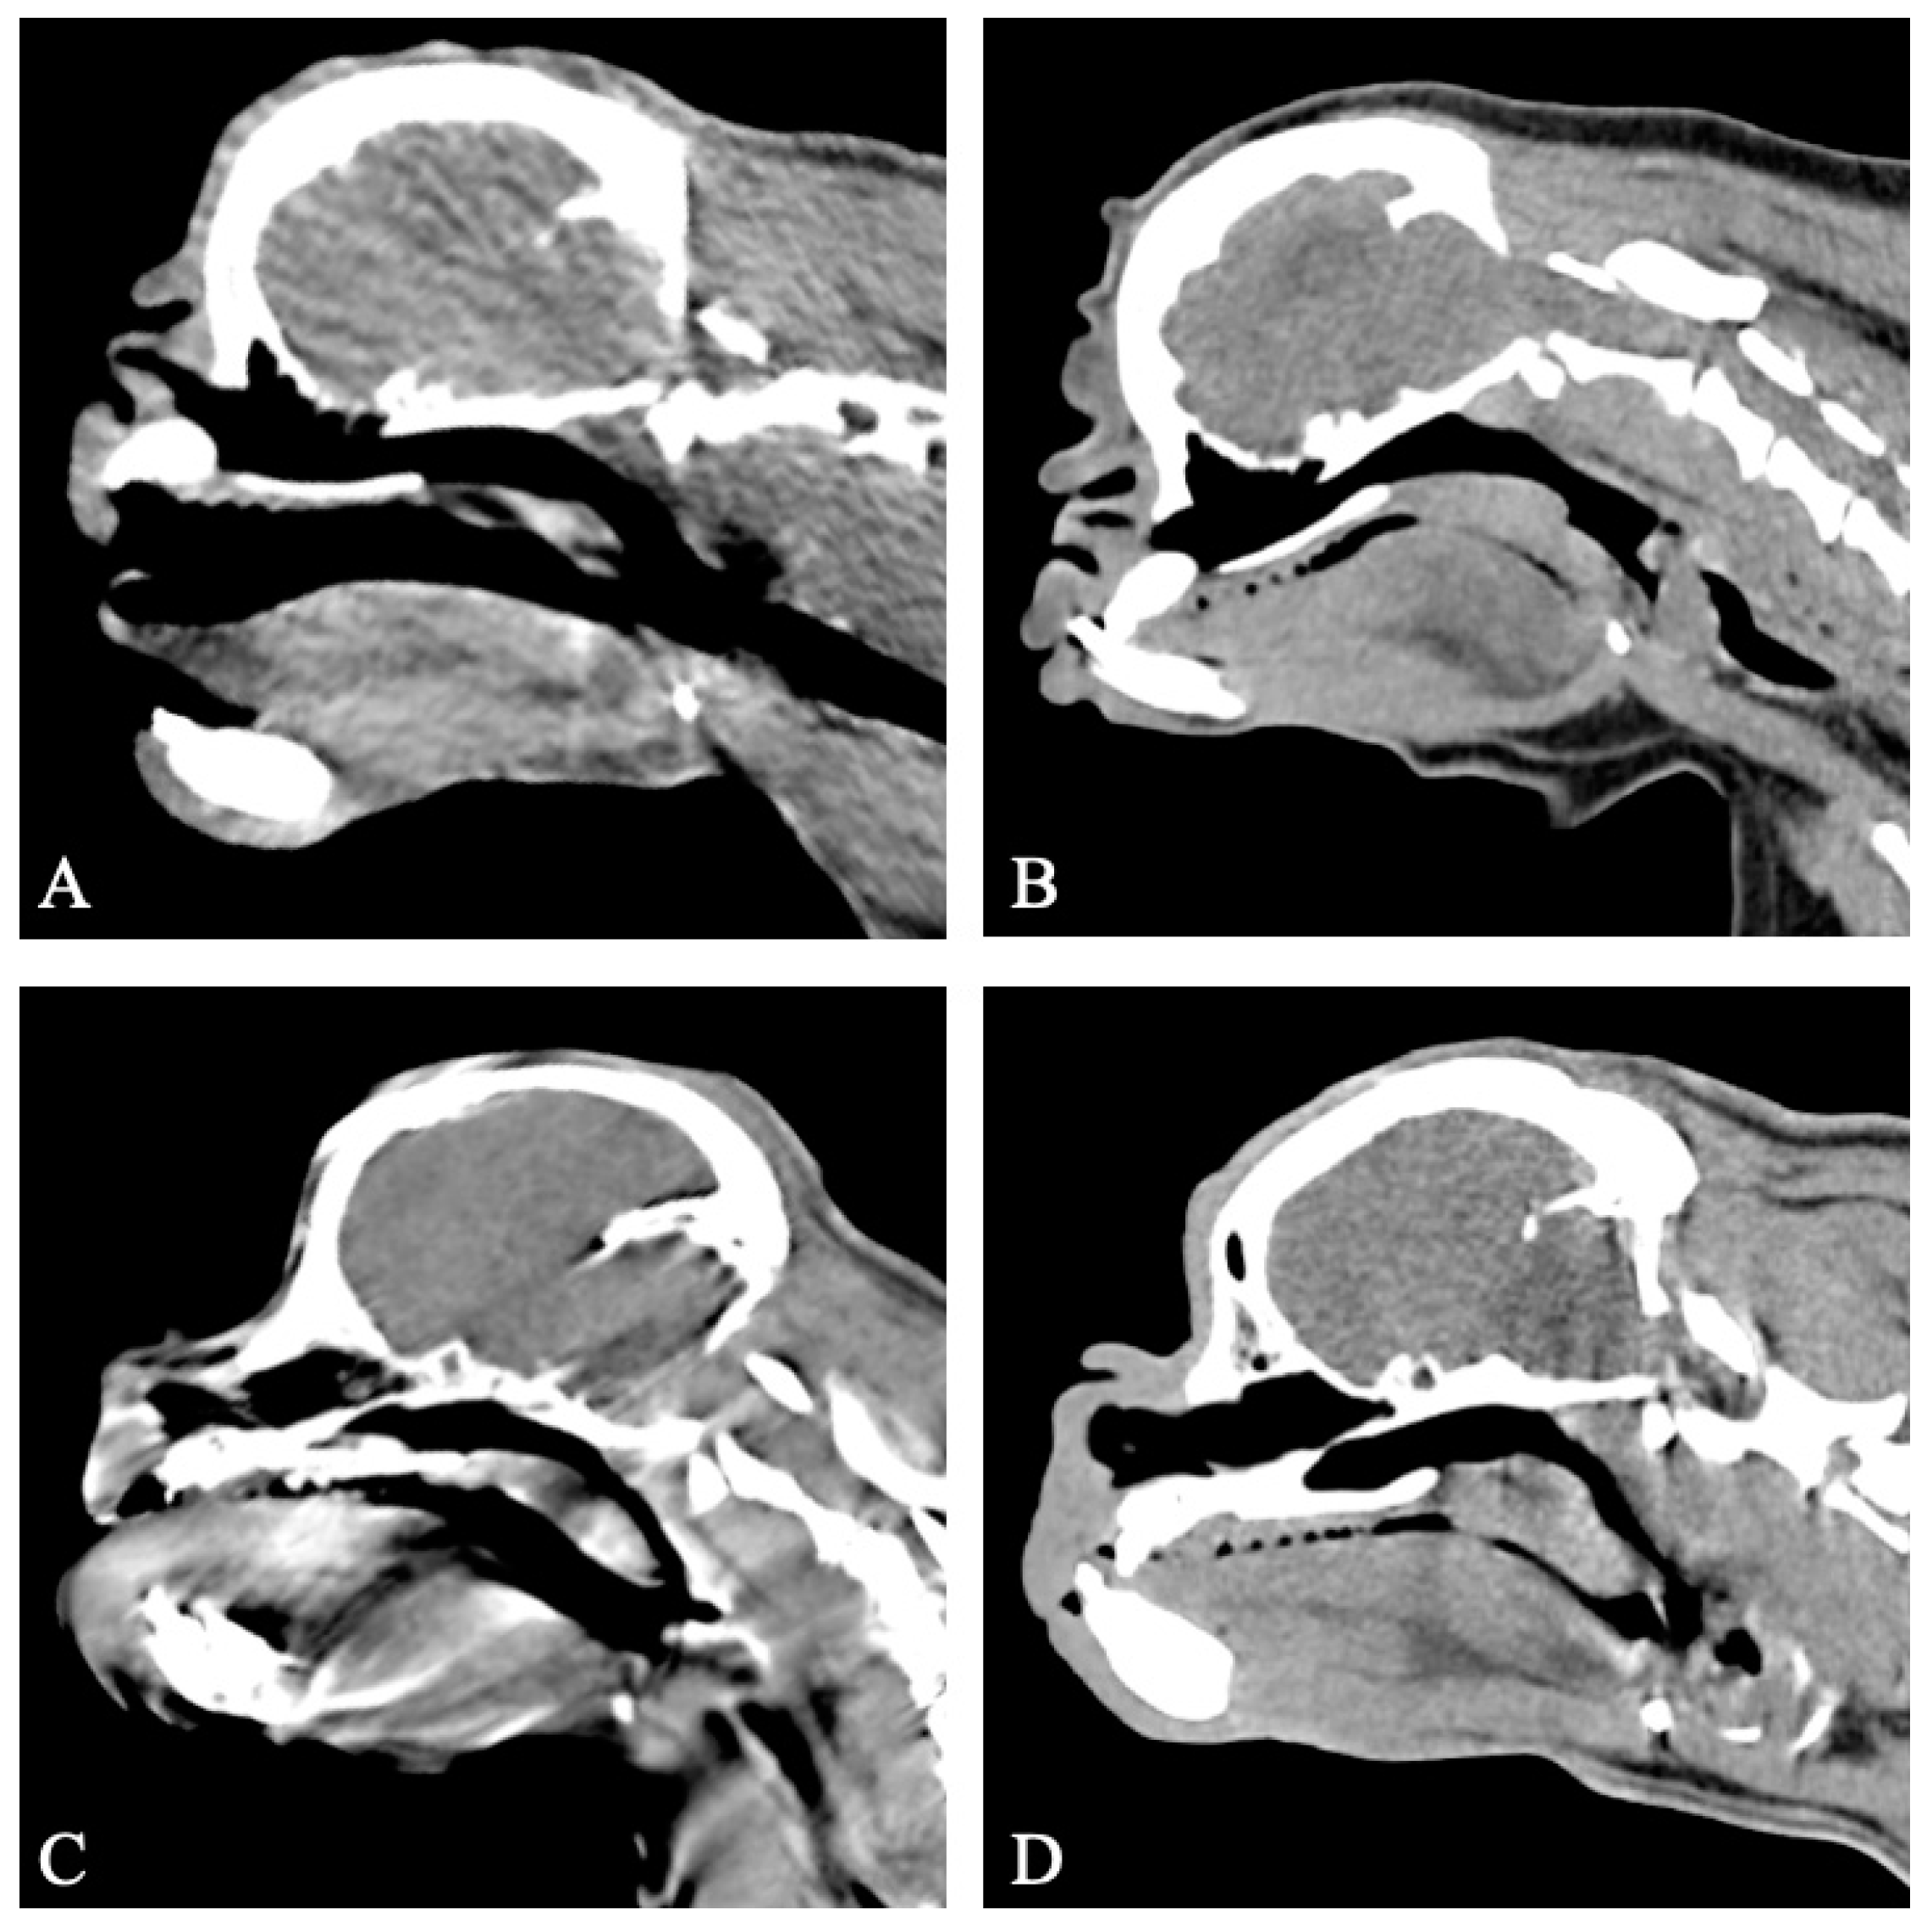

The CT provided diagnostic images for all four patients for the evaluation of the soft palate and nasopharynx, with mild motion artifacts in two patients. All of the four dogs had a soft palate of normal length (Figure 4). Thickening of the soft palate was assessed as normal (n = 1), mild (n = 2) and moderate (n = 1) based on the extent of nasopharyngeal obstruction (Figure 4).

Figure 4. Sagittal non-contrast CT images of the skull of four patients previously treated for BOAS (group II). All patients have a normal soft palate length. All patients display varying degrees of soft palate thickening. (A) Case 5, normal soft palate thickness. (B) Case 17, mild soft palate thickening. (C) Case 14, mild soft palate thickening. (D) Case 1, moderate soft palate thickening. Window width, 400 HU; window level 40 HU; 1 mm slice thickness.